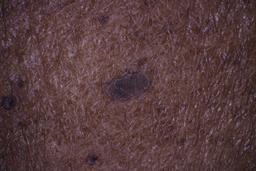

ISIC_6598546

Clinical

| Field | Value |

|---|---|

| age_approx | 60 |

| anatom_site_1 | Trunk |

| anatom_site_2 | Posterior trunk |

| concomitant_biopsy | False |

| dermoscopic_type | contact polarized |

| diagnosis_1 | Benign |

| diagnosis_confirm_type | single contributor clinical assessment |

| fitzpatrick_skin_type | VI |

| image_manipulation | instrument only |

| image_type | dermoscopic |

| lesion_id | IL_6711989 |

| patient_id | IP_8590441 |

| sex | male |